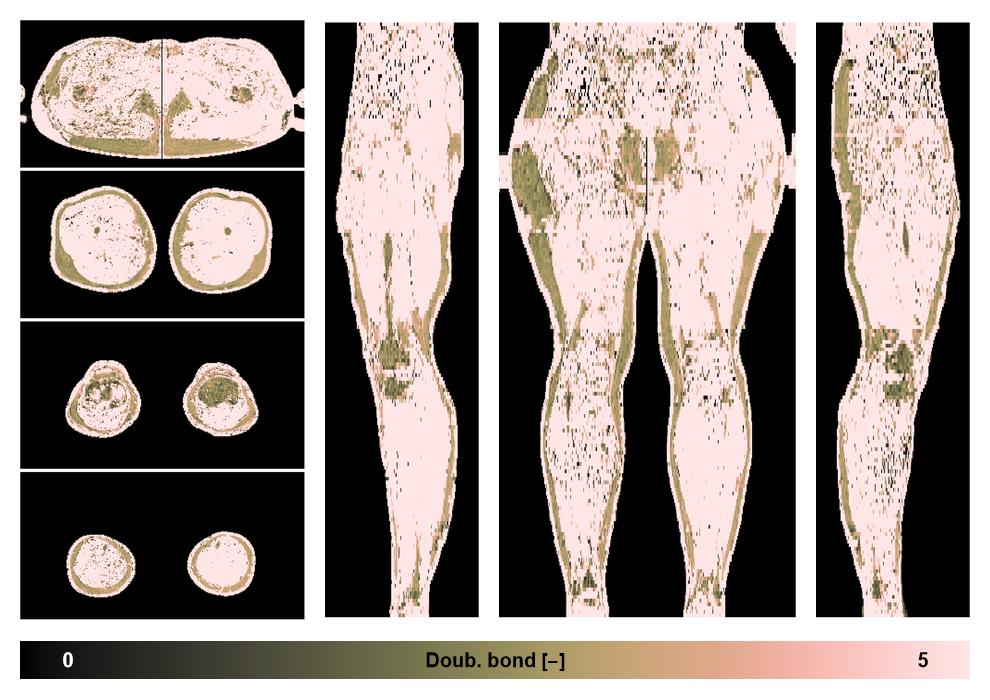

• Number of double bonds in subcutanious fat

Number of double bonds in subcutanious fat.